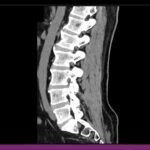

Lembrando que nosso canal nós falamos sobre diversos temas relacionados à dor nas costas, hérnia de disco, entre outras disfunções da coluna vertebral do corpo humano. E para lembrar que fizemos vários vídeos a respeito sobre sintomas de hérnia de disco e talvez você nem saiba, basta clicar aqui no card e assistir o vídeo. E voltando ao tema sobre os cinco sinais e sintomas que você pode estar apresentando e nem sabe que é um sinal grave da hérnia de disco.

- A fraqueza muscular, também chamada de paresia: quando você não consegue realizar um movimento específico porque o seu membro, ou a parte do seu corpo não está correspondendo, é como se ele fosse de graça. E de forma bem precoce. O exemplo bem simples é ao levantar da cadeira, os pacientes relatam que perde a força nas pernas para levantar da cadeira, para subir uma escada, subir degrau, para também entrar no carro, sair do carro, movimentos do dia a dia, você começa a perceber que você não tem mais tanta força como você tinha antes. Isso é um sinal bem forte e grave da hérnia de disco, que é a fraqueza muscular.

- O segundo sintoma que também apresenta é a dormência e formigamento, aquela sensação como se tivesse uma formiguinha andando pelas suas pernas, pelas suas mãos. Também muitos casos apresentam uma perda de sensibilidade, é como se você tocasse, batesse lá em algum lugar e você não sentisse aquela parte da sua mão, por exemplo, ou até no seu pé. Também em muitos casos bem específicos, muitos pacientes relatam que, exatamente na borda lateral do pé, não conseguem sentir aquele sentimento, formigamento, muita dormência. Isso é um sinal de que o disco está entre as vértebras da coluna está comprimido de forma severa e está apresentando esse sintoma.

- O terceiro sinal e sintoma é quando o paciente não consegue ficar ereto, ou seja, ele mantém uma postura antálgica, é uma postura que você corrige que você sente tanta dor, que muitas vezes os pacientes chegam aqui na clínica curvados. Eles não conseguem ficar eretos porque incomoda muito. Muitas vezes essa dor começa a irradiar e apresentar aqueles outros sintomas como formigamento, dormência na perna. Em outros casos, também, eles apresentam escoliose antálgica, e aquele desvio postural do paciente, ficar literalmente torto, ele não consegue ficar reto. Não é porque ele não queira, é porque ele sente muita dor e desconforto ao tentar corrigir essa postura.

- O quarto sinal e sintoma é disfunção urinária ou até intestinal. Isso parece até meio estranho, mas também é um sinal crítico. Os nervos só não vão para as pernas, para as mãos, para os músculos, eles também vão levar as informações para as vísceras, como a bexiga, que faz parte do trato urinário, o intestino. Então, se você apresenta uma dificuldade para urinar, uma dificuldade para prender o xixi, ou seja, você não consegue controlar a vontade de evacuar, isso também é um sintoma grave da hérnia.

- O quinto e último sinal e sintoma é aquele tipo de paciente que já tomou vários medicamentos muito fortes e que inclusive foi ao hospital tomar medicação injetável, analgésico, anti-inflamatório e relaxante muscular, até antidepressivos, e não teve resultado. Muitas vezes o problema não é apenas bioquímico, é mecânico. Portanto, se você apresenta sintomas, ou conhece alguém que está apresentando esses sintomas, pode ser sim o indicador que sua hérnia de disco pode ser muito grave e, portanto, você deve procurar um especialista o quanto antes.